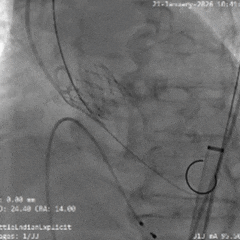

术中影像

根部造影

瓣叶钙化明显,瓣叶活动差,中度反流

直头导丝顺利跨瓣

猪尾导管测量跨瓣压差约60mmHg

20mm球囊预扩

小弯侧微腰,少量漏,左冠显影,右冠无显影

瓣膜0位初始定位释放

全展开位造影评估

瓣下约 3mm,左右冠均显影,少量反流

瓣膜稳定脱钩

无位移,无弹跳,无张力释放

根部造影评估

位置可,形态受限,可见中重度反流,左右冠均显影

20mm球囊后扩

可见瓣架底端扩开,瓣膜形态改善

最终造影可见瓣周漏,符合术前预判

超声可见左无对合缘轻度反流,整体瓣架形态较圆,左无钙化处呈“D”型,测量峰值流速为1.6m/s